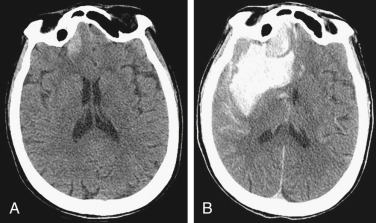

SDH